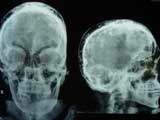

A 66-year-old male was suffering from Paget's disease since 1999. He developed a stress fracture of the left thigh bone in January 2006. The patient was referred in May 2006 as fracture healing was not satisfactory. He was administered two intravenous injections of pamidronate and was prescribed risedronate 35 mg weekly later on. Both of these belong to the amino bisphosphonate group of drugs used to treat active Paget's disease. The fractures healed. The patient did not visit a rheumatologist and continued to take risedronate till November 2008.